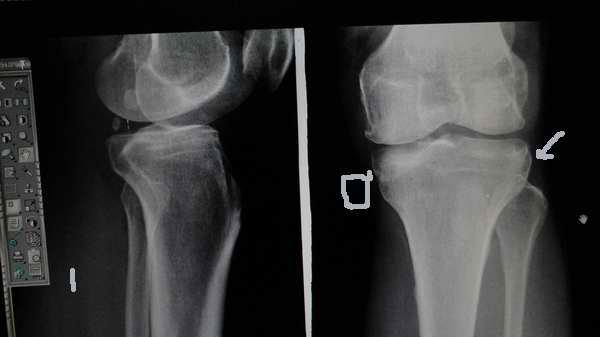

标题: 第二例病人,外伤线上的是不是平台陈旧性骨折

2、感觉不像平台的陈旧骨折。

第二例:膝关节退行性改变;不排除内侧平台陈旧性骨折。

第二位病人,内侧平台陈旧性压缩骨折可能性大,建议ct。

第二例考虑退行性改变。

第一个病例报告时要提示膝关节间隙馁窄外宽改变,建议结合临床或进一步检查,第二个病例支持考虑胫骨平台骨折后改变。

第一例可报:内窄外宽改变,建议mri检查。第二例考虑有胫骨平台陈旧性骨折